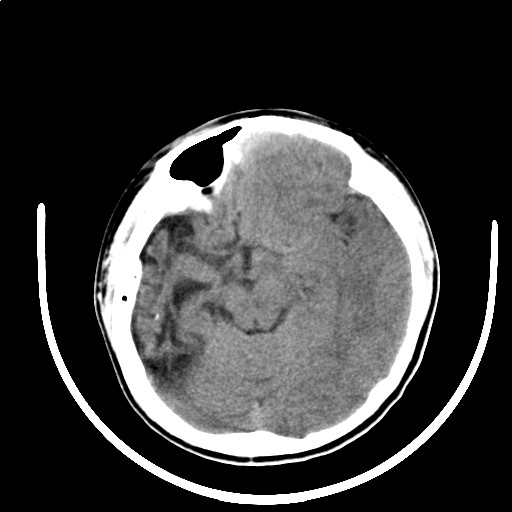

标题: PED3416:F,12Y,智力下降,学习成绩差,8个月时发过高烧。

右侧半球萎缩,软化,多量脑回样钙化,考虑颅面血管瘤病,建议dsa检查

右侧半球萎缩,软化,多量脑回样钙化,同侧颅盖板障增宽,考虑颅面血管瘤病,建议dsa检查与化脓性脑膜炎后遗改变鉴别。